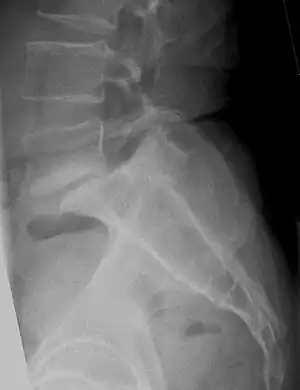

| X-ray of the lateral lumbar spine with a grade III anterolisthesis at the L5-S1 level. | |